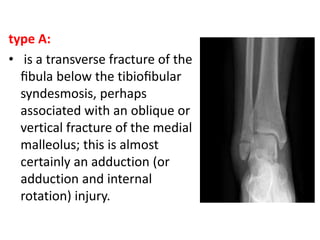

type A:

• is a transverse fracture of the

fibula below the tibiofibular

syndesmosis, perhaps

associated with an oblique or

vertical fracture of the medial

malleolus; this is almost

certainly an adduction (or

adduction and internal

rotation) injury.

type A: • isa transverse fracture of the fibula below the tibiofibular syndesmosis, perhaps associated with an oblique or vertical fracture of the medial malleolus; this is almost certainly an adduction (or adduction and internal rotation) injury.